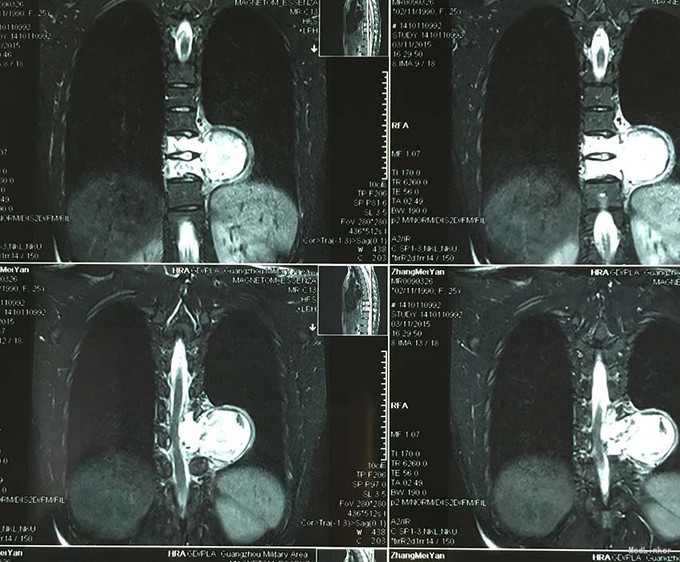

查体:脊柱外观无明显畸形,颈椎活动度正常,胸背部可见纵向长约15cm切口,皮肤钉缝合,伤口愈合可,无红肿渗液。胸椎9-10体左侧棘突旁局部压痛(+)、叩击痛(-),压头试验阴性,双侧侧臂丛牵拉实验(-),双上肢肌张力、运动、感觉及反射无明显异常、躯体感觉无明显减退,双下肢髂腰肌、股四头肌、胫前肌肌力IV级,感觉正常,双下肢直腿抬高试验(-),双侧腱反射对称略活跃,双侧Hoffman征(-),双侧Babinski征(-),双侧髌阵挛(-),踝阵挛(-)。 辅助检查:2015-11外院胸椎MRI检查发现T9-10节段椎体肿瘤并椎旁软组织肿块形成,肿块突入胸腔占位

诊断:胸椎椎体肿瘤(T9-10) 治疗:先于外院行1期后路椎弓根钉固定融合手术,然后转入我院行介入下术前椎体节段血管栓塞手术,第二天行经左侧胸腔入路椎体肿瘤病灶刮除并钛网植骨植入重建手术。术后恢复满意。复查MRI显示肿瘤病灶基本完全切除。